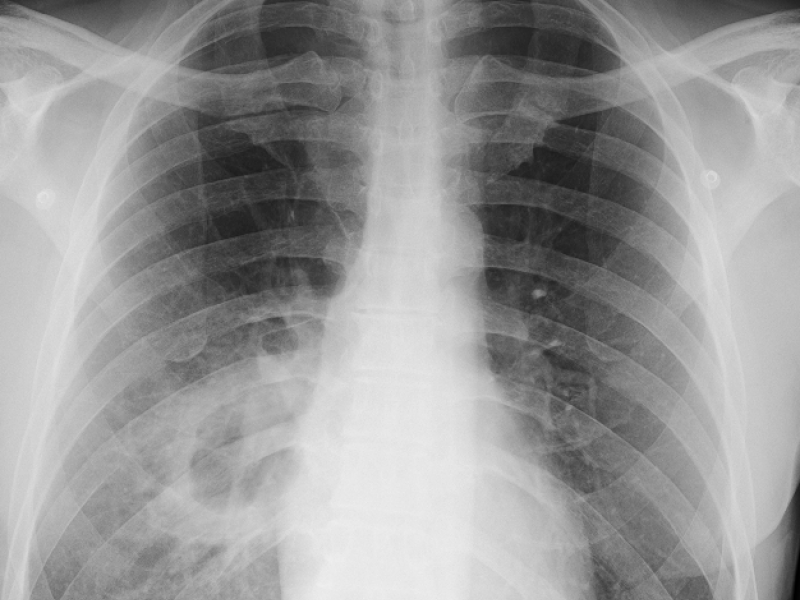

A 53 yo M w/ a remote history of TB, prior IVDU and